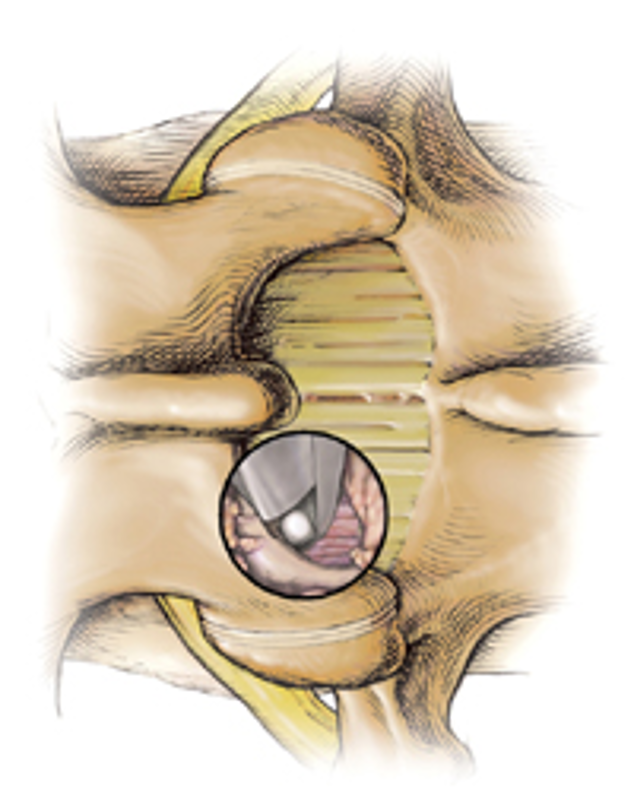

后路椎间盘镜下髓核摘除术

技术特点采用微创技术,皮肤创口仅1.5cm左右,不剥离椎旁肌,保留棘上、棘间韧带和大部分上、下关节突以及未破损的纤维环和后纵韧带,尽可能保持脊柱的稳定性。去除了突出的髓核组织、肥厚的黄韧带及增生内聚的关节突等神经致压因素,从而使患者获得根治的疗效。

手术通道安装

将定位针置于上位椎板下缘骨质上,防止插入肌肉扩张管时将导针推入椎管内。

用扩张管来回刮擦椎板及黄韧带外软组织,直到出现骨擦感。这样可以减少通道内软组织。

通道管的方向:矢状面与椎间隙平行,横断面大致与棘突平行、与椎板垂直。

进入椎管方法

椎板间隙入路:1、椎板下方入路;2、椎板下缘关节突内侧入路

黄韧带在椎板下缘处最薄弱,而椎管内以神经根外上方(肩部)最安全,因此最常选用椎板下缘关节突内侧入路。

冲洗和抽吸

冲洗可以清洁镜头、止血、防雾等。

小心使用带吸引器的拉钩,避免长时间放置在硬膜囊表面,防止发生蛛网膜疝出、硬脊膜撕裂。

通道内放置一个细小皮管,连接吸引器。可以有效去除管道内气雾。